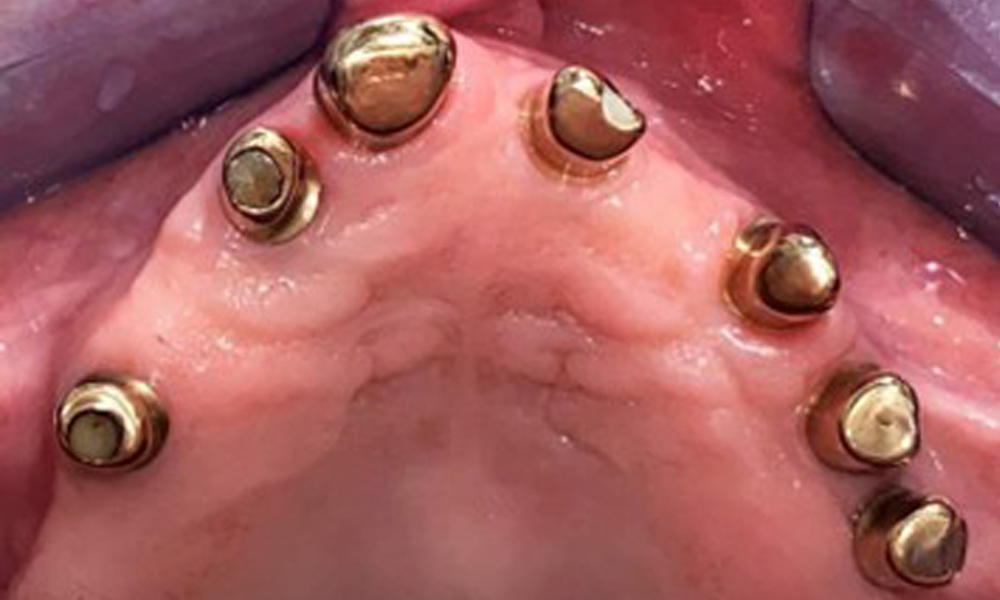

Okklusalansicht: Oberkiefer mit Zahn- und implantatgetragenen Teleskopen.

Abb. 2: Okklusalansicht: Oberkiefer mit Zahn- und implantatgetragenen Teleskopen.